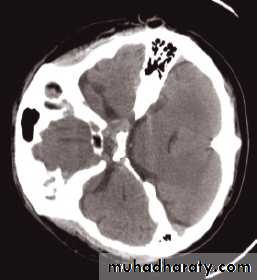

Enlargement of ventricles

There are two basic mechanisms which cause the cerebral ventricles to enlarge:• Obstruction to the CSF pathway, either within the ventricular system (non-communicating hydrocephalus) or over the surface of the brain (communicating hydrocephalus)

• Secondary to atrophy of brain tissue